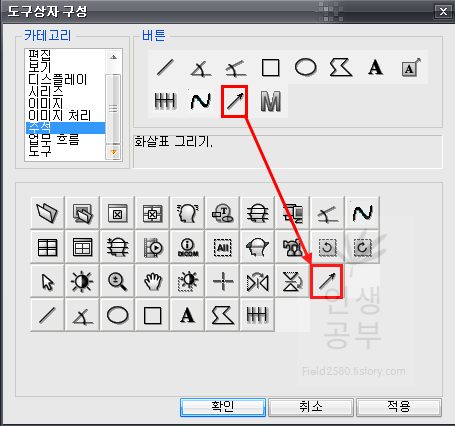

그 다음으로 많이 사용하는 화살표 버튼을 추가해줍니다. 환자에게 설명할 때 포인트를 줄 때 많이 사용하니 추가해주시는 걸 추천해드립니다.

카테코리에 있는 모든 버튼을 보시는 것을 추천합니다. 위에 설명해드린 것은 제가 환자들과 함께 X-ray보면서 많이 사하는 것들이니 사용자에 따라서 선호하는 것들이 다를 수 있으니 한번 모두 다 보시고 추가할 것들은 추가하고 제거할 것들은 제거해주시는 것이 좋습니다. 카테고리에 있는 메뉴를 누르면 해당 메뉴에 버튼이 나오게됩니다. 이 버튼에 마우스를 가져대면 아래에 짧은 설명이 나오니 참고해주시기바랍니다. 어짜피 시간이 지나면서 잘 안쓰는 것들은 삭제하게 되니 필요에 따라서 삭제할 수도 있고, 필요한 것들은 다시 추가할 수 있으니 너무 많이 고민하지 않으셔도 됩니다. 본인에 맞게 메뉴가 세팅이 되었으면 적용버튼을 눌러줍니다.